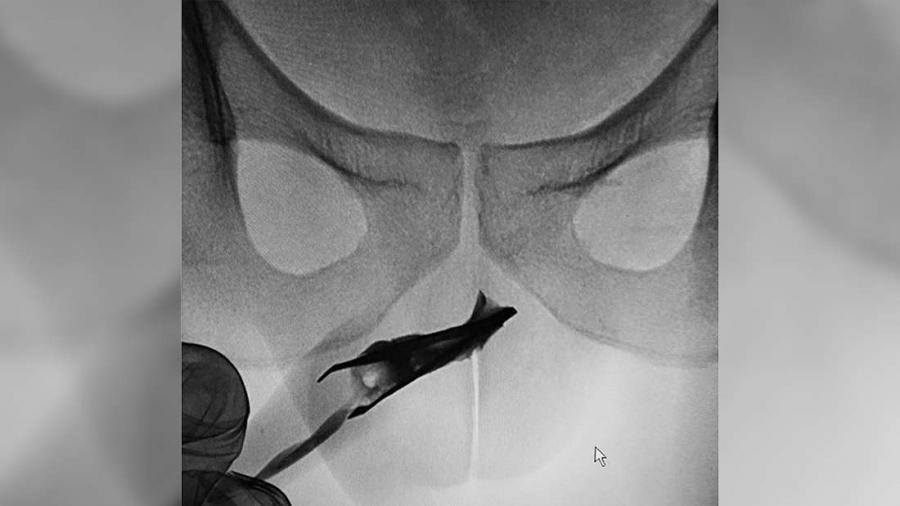

През 2015 г. 18-годишен младеж решава да заклещи метални пинцети в своя пенис. 4 години по-късно той решава да посети лекар с твърдението, че те въобще не са му причинявали каквито и да било проблеми.

Освен че не е изпитал нито един от очакваните симптоми (като възпаление или треска), мъжът е можел да уринира нормално, въпреки че в пикочния му канал (пренасящ урината и спермата извън тялото), е имало 8-сантиметрови пинсети.